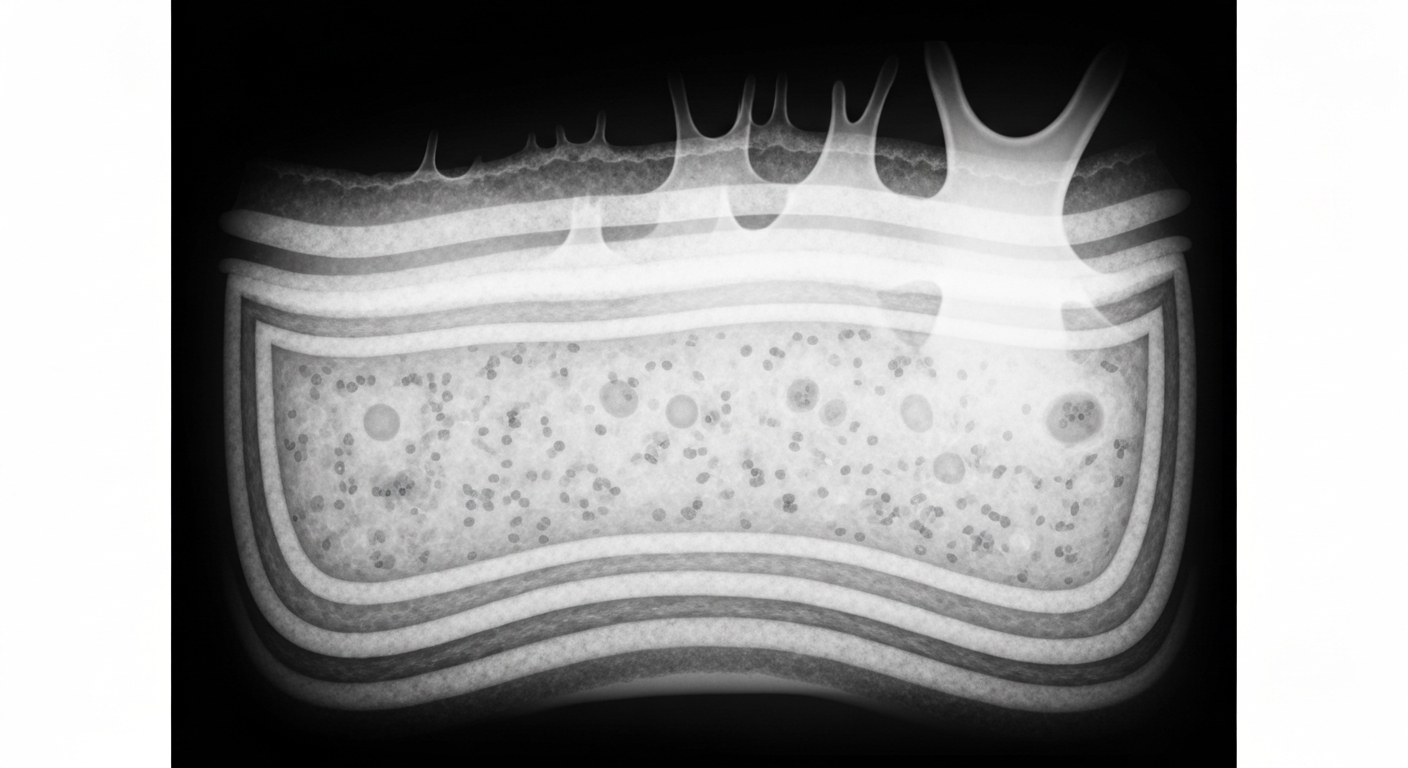

Minimally invasive tape strips provide a window into the molecular underpinnings of rare ichthyosis skin disorders.Mount Sinai TodayA pilot study evaluating minimally invasive tape-strip RNA sequencing found shared upregulation of Th17/Th22 immune markers and increased cornified envelope/epidermal differentiation complex (EDC) gene expression across all orphan ichthyosis subtypes, including Netherton syndrome, congenital ichthyosiform erythroderma, lamellar ichthyosis, and epidermolytic ichthyosis.

This study highlighted the feasibility of using tape strips to measure the immune and barrier abnormalities in these rare ichthyosis conditions, which predominantly affect children and have heterogeneous treatment responses. The minimally invasive sampling method may enable longitudinal monitoring of disease changes with treatment in future clinical trials.

Researchers collected tape strip RNA sequencing data from 27 patients with ichthyosis and 18 demographically matched healthy controls at Mount Sinai and Northwestern University. The cohort included 9 patients with Netherton syndrome, 6 with congenital ichthyosiform erythroderma, 7 with lamellar ichthyosis, and 5 with epidermolytic ichthyosis. RNA was extracted from 20 consecutive tape-strip samples per individual and analyzed using RNA-seq. All ichthyosis subtypes demonstrated significant upregulation of Th17-associated and Th22-associated markers, with Netherton syndrome showing unique Th2 dysregulation. Disease severity correlated with ceramide synthase 3, Th17 markers, and late cornified envelope genes.